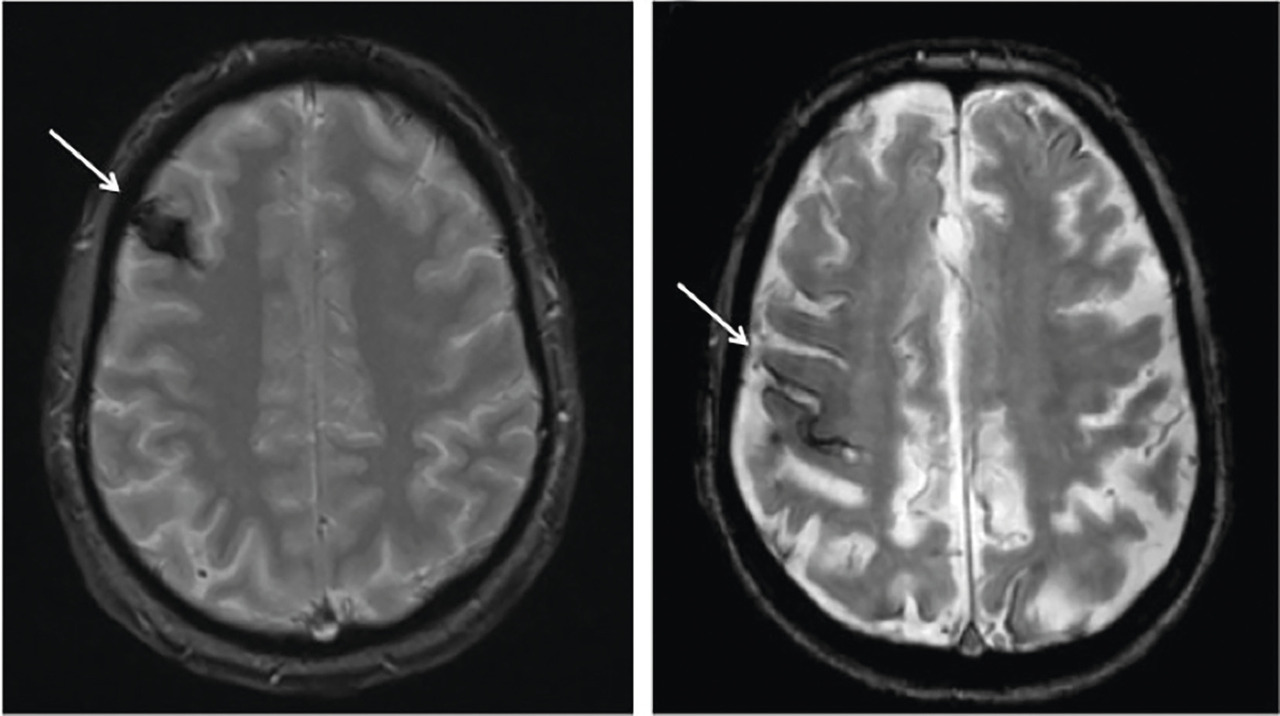

En effet, dans 5 % des cas, le déficit neurologique transitoire est dû à une hémorragie intracérébrale (fig. 1a, malformation vasculaire : cavernome) ou à d’autres maladies à risque hémorragique (fig. 1b, angiopathie amyloïde cérébrale).

Les principaux sont l’hypoglycémie, la crise épileptique partielle et l’aura migraineuse (tableau 1). L’examen clinique peut contribuer à les éliminer. L’IRM encéphalique (encadré 1) est un examen précieux pour poser le diagnotic (fig. 1).

L’IRM encéphalique est préférable à la tomo- densitométrie (TDM) parce que, contrairement à celle-ci, elle montre les lésions hémorragiques anciennes de petite taille.

La séquence de diffusion est indispensable ainsi que celle dite T2*-écho de gradient (encadré 1).

1. Intérêt de l’IRM encéphalique dans la pathologie neurovasculaire

Séquence de diffusion (DWI, Diffusion Weighted Imaging) : l’hypersignal traduit le ralentissement de la mobilité des molécules d’eau secondaire aux lésions ischémiques avec présence d’un œdème cytotoxique dès les premières minutes. La cartographie du coefficient apparent de diffusion (ADC, Apparent Diffusion Coefficient) permet une évaluation quantitative du mouvement, diminué (restriction), en cas d’ischémie.

Séquence T2*-écho de gradient : l’hyposignal traduit la présence d’hémosidérine, produit de dégradation de l’hémoglobine. Cette séquence permet la mise en évidence d’une hémorragie intracrânienne.

Autres séquences : FLAIR (évaluation morphologique du parenchyme cérébral) et ToF (imagerie vasculaire, notamment du polygone de Willis, sans injection de produit de contraste).